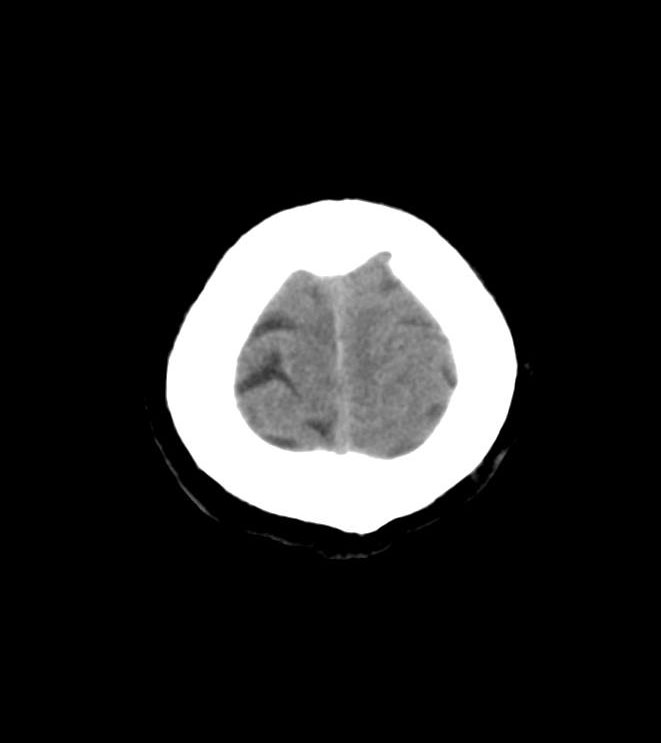

神津仁の名論卓説 - 一過性全健忘 Transient Global Amnesia

f:id:jyoutoubyouinsougounaika:20180404194741p:plain